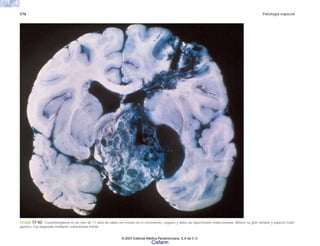

FIGURA 2-2. Esquema de la molécula de procolágena y de las modificaciones que la transforman en una molécula de colágena insoluble. (Tomado de Procop DJ y cols. New Eng J. Med.

301: 13, 77, 1979.)